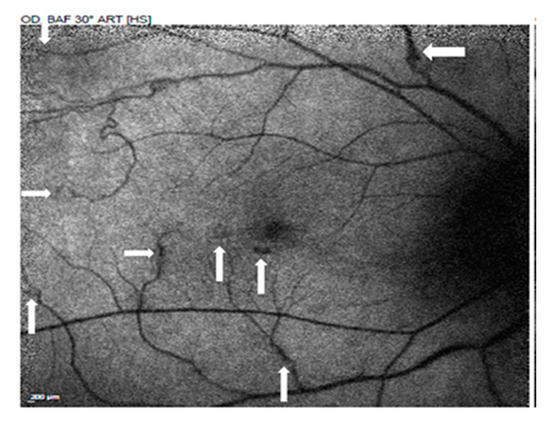

Multimodal Imaging in the Management of Choroidal Neovascularization Secondary to Central Serous Chorioretinopathy

by Ahmed M. Hagag, Shruti Chandra, Hagar Khalid, Ali Lamin, Pearse A. Keane, Andrew J. Lotery and Sobha Sivaprasad

J. Clin. Med. 2020, 9(6), 1934; https://doi.org/10.3390/jcm9061934 - 21 Jun 2020

The diagnosis and treatment of choroidal neovascularization (CNV) in eyes with chronic central serous chorioretinopathy (CSCR) can be challenging. The purpose of this study was to classify eyes with suspected CNV using multimodal imaging. The effect of intravitreal anti-vascular endothelial growth factor (VEGF) [...] Read more.

The diagnosis and treatment of choroidal neovascularization (CNV) in eyes with chronic central serous chorioretinopathy (CSCR) can be challenging. The purpose of this study was to classify eyes with suspected CNV using multimodal imaging. The effect of intravitreal anti-vascular endothelial growth factor (VEGF) was assessed and compared to controls. This retrospective study included chronic CSCR patients with suspected secondary CNV who received intravitreal bevacizumab. Eyes were divided into “definite CNV” and “no CNV” based on optical coherence tomography angiography (OCTA). Eyes that did not undergo OCTA imaging were considered as “presumed CNV”. One-year outcome in visual acuity (VA) and central foveal thickness (CFT) were investigated and compared to non-treated control patients to assess the response to anti-VEGF. Logistic regression analysis was used to explore predictive biomarkers of CNV detection and improvement after anti-VEGF. Ninety-two eyes with chronic CSCR from 88 participants were included in this study. Sixty-one eyes received bevacizumab and 31 eyes were non-treated control subjects. The presence of subretinal hyperreflective material (SHRM) and shallow irregular retinal pigment epithelium (RPE) elevation (SIRE) with sub-RPE hyperreflectivity on OCT was associated with a significantly increased risk of detecting CNV on OCTA. Intravitreal anti-VEGF caused significant functional and anatomical improvement in patients with neovascular CSCR as compared to non-treated eyes. In contrast, VA and CFT changes were not significantly different between treated and non-treated CSCR with no evidence of CNV on OCTA. No clinical or anatomical biomarkers were found to be associated with response to treatment. In conclusion, OCTA should be used to confirm the presence CNV in suspected chronic CSCR patients. Intravitreal anti-VEGF treatment resulted in a significantly better one-year outcome in patients with definitive OCTA evidence of CNV. Full article